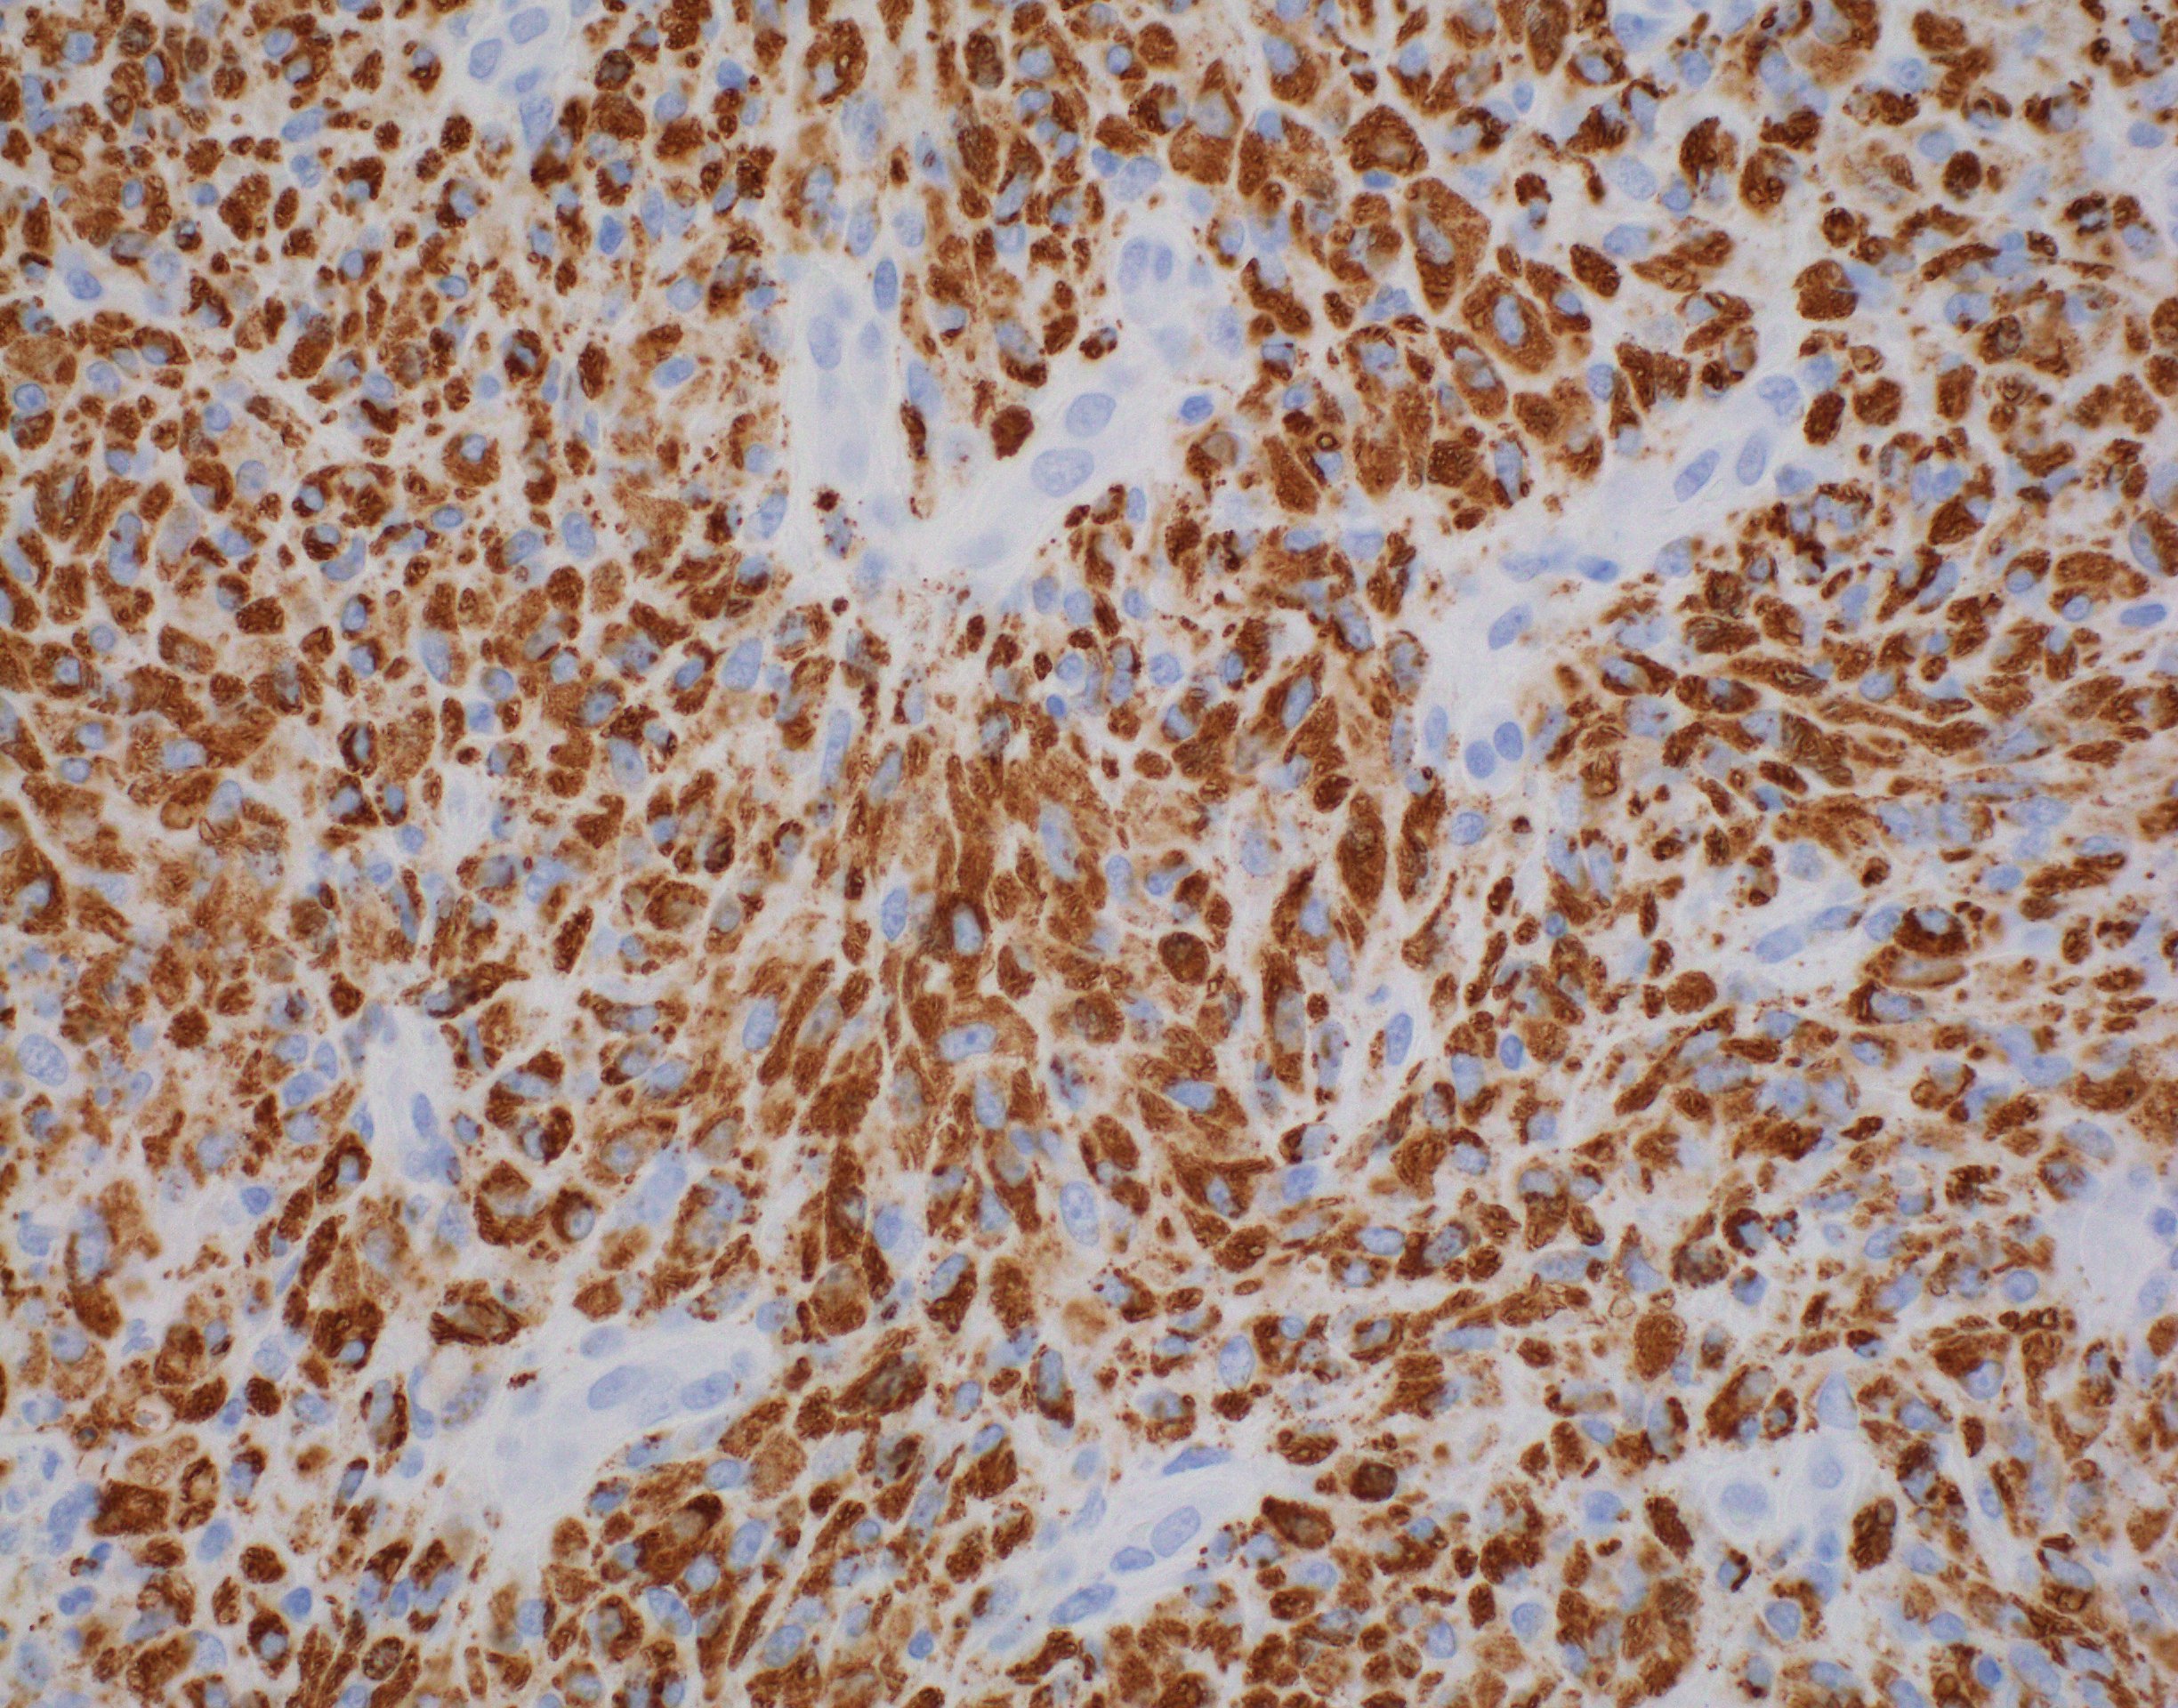

Microscopic (histologic) description

- Nodes show partial / complete effacement by storiform pattern of bland spindle cells, some with vacuoles

- Numerous vessels lined by plump endothelial cells, plasma cells and lymphocytes

- No multinucleated tumor cells, no foamy histiocytes

Microscopic (histologic) images

Contributed by AFIP and Chunyu Cai, M.D., Ph.D. (Case #532)

Positive stains

- Kaposi sarcoma:

- Fascicular spindle cells, slit-like spaces, mitotic figures, no granular or acidophilic cytoplasm

- Spindle cells are CD31+ and CD34+

- S100- and CD68- (Am J Surg Pathol 1999;23:656)